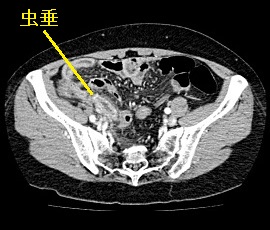

[急性虫垂炎] 手術:腹腔鏡下虫垂切除術(虫垂周囲膿瘍を伴う)

急性腹症のため救急受診。精査の結果、急性虫垂炎と診断。緊急手術(虫垂周囲膿瘍を伴う腹腔鏡下虫垂切除術)を施行した。病理診断結果は急性化膿性虫垂炎であった。

CT画像